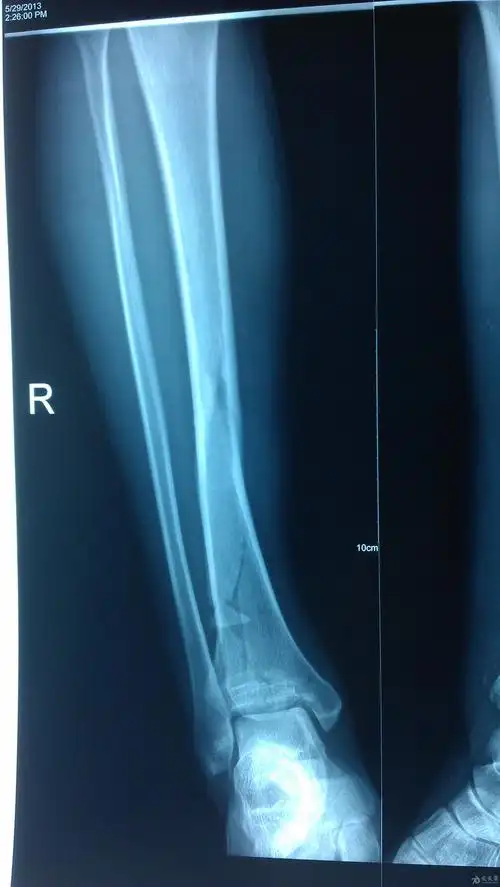

一例不用担心后踝有骨折的胫骨中下段螺旋形骨折

21岁 女 胫骨螺旋性骨折 需要手术么 有x片

胫骨远端长螺旋形粉碎性骨折

胫骨远端螺旋形骨折手术髓内钉治疗分享

胫骨下段腓骨上段螺旋形骨折的治疗方案

曹某某,男,15岁,诊断:右胫腓骨螺旋形骨折,闭合复位mipo接骨板技术内

胫骨下段螺旋骨折闭合复位髓内钉阻挡钉技术

胫腓骨粉碎性螺旋形骨折